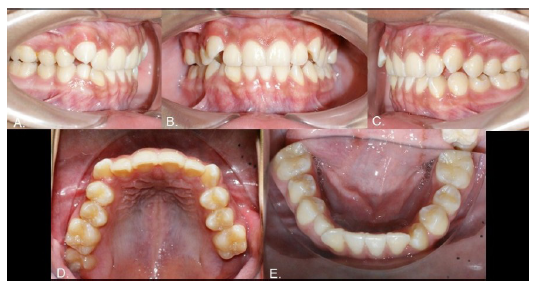

Case 4

Male, 25 years of age. Both the 2.3 and 4.3 were absent, with corresponding gaps, and the 2.2 was microdontic (Fig. 7). The radiograph showed that both missing teeth were in transmigration (Fig. 8A) and the inferior one was a type 2 transmigration. The patient decided on monitoring for both teeth to allow orthodontic treatment to open the spaces and then restore the errant canines to their places. The 2.5-year follow-up panoramic x-ray showed no significant changes (Fig. 8B).